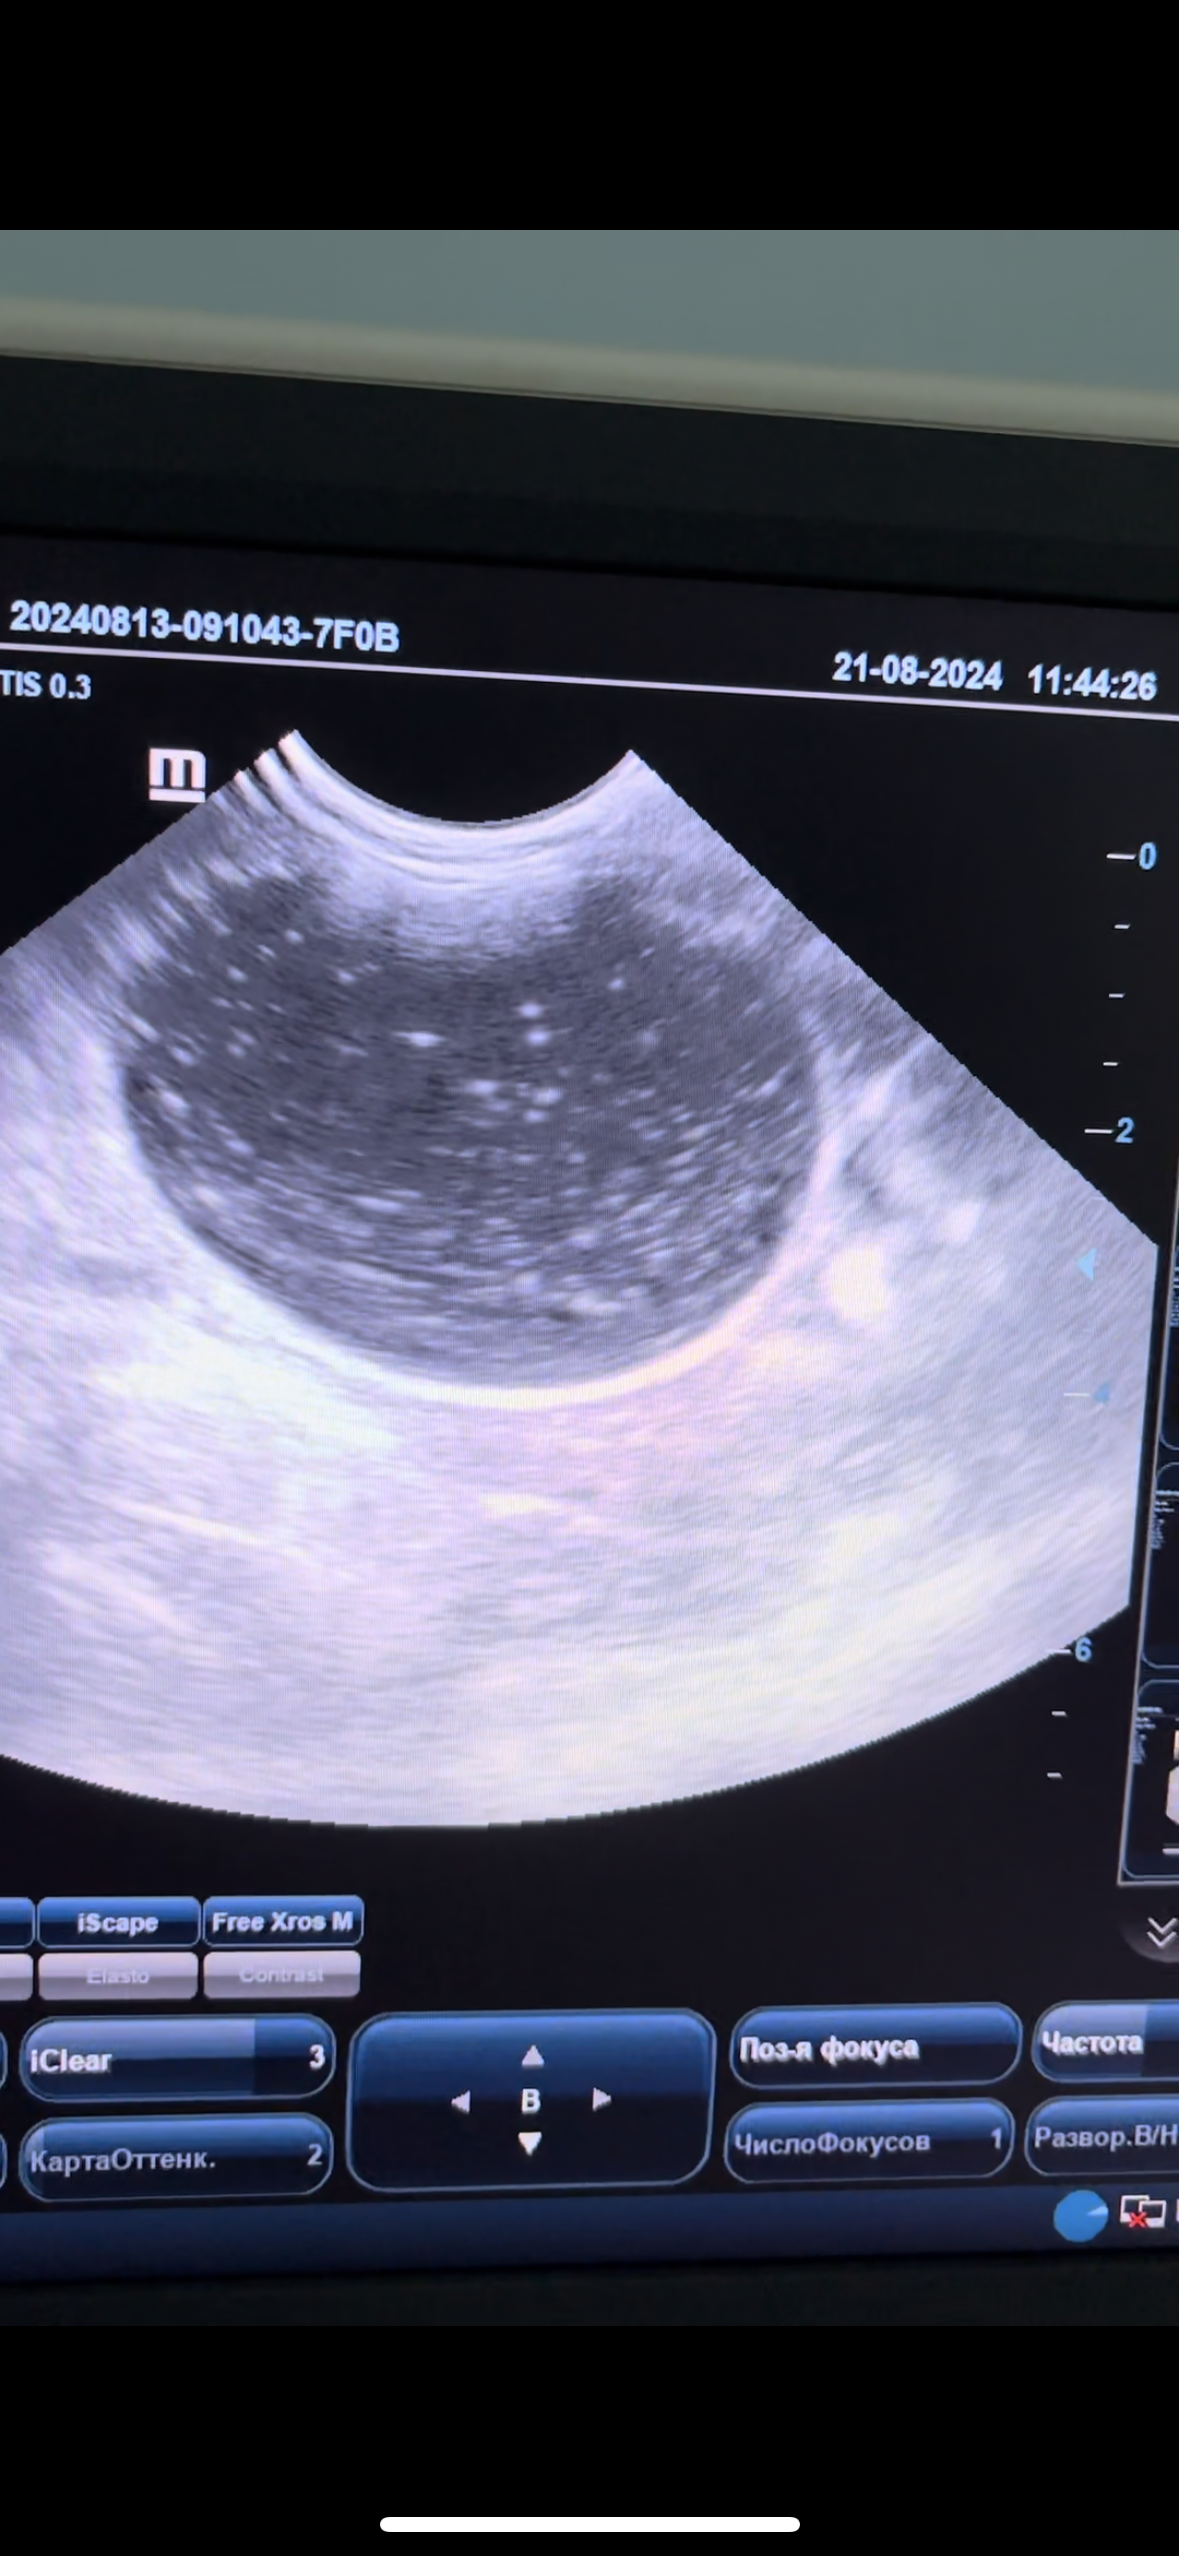

В конце сентября текущего года в участковую ветеринарную лечебницу по адресу: г. Саратов, ул. Соколовая, д. 314/79 обратился владелец с котом по кличке «Том», возраст 2,5 года. У животного наблюдались такие жалобы как частое мочеиспускание, болевой синдром, отказ от еды. Ветеринарными врачами было проведено УЗИ, которое показало огромное количество мелкодисперсной взвеси и поставлен диагноз - мочекаменная болезнь, уроцистит и общий анализ мочи, который выявил наличие трипельфосфатов в моче. Домашнему питомцу назначено лечение: диета, специальные корма, контроль мочи и УЗИ через 12дней.